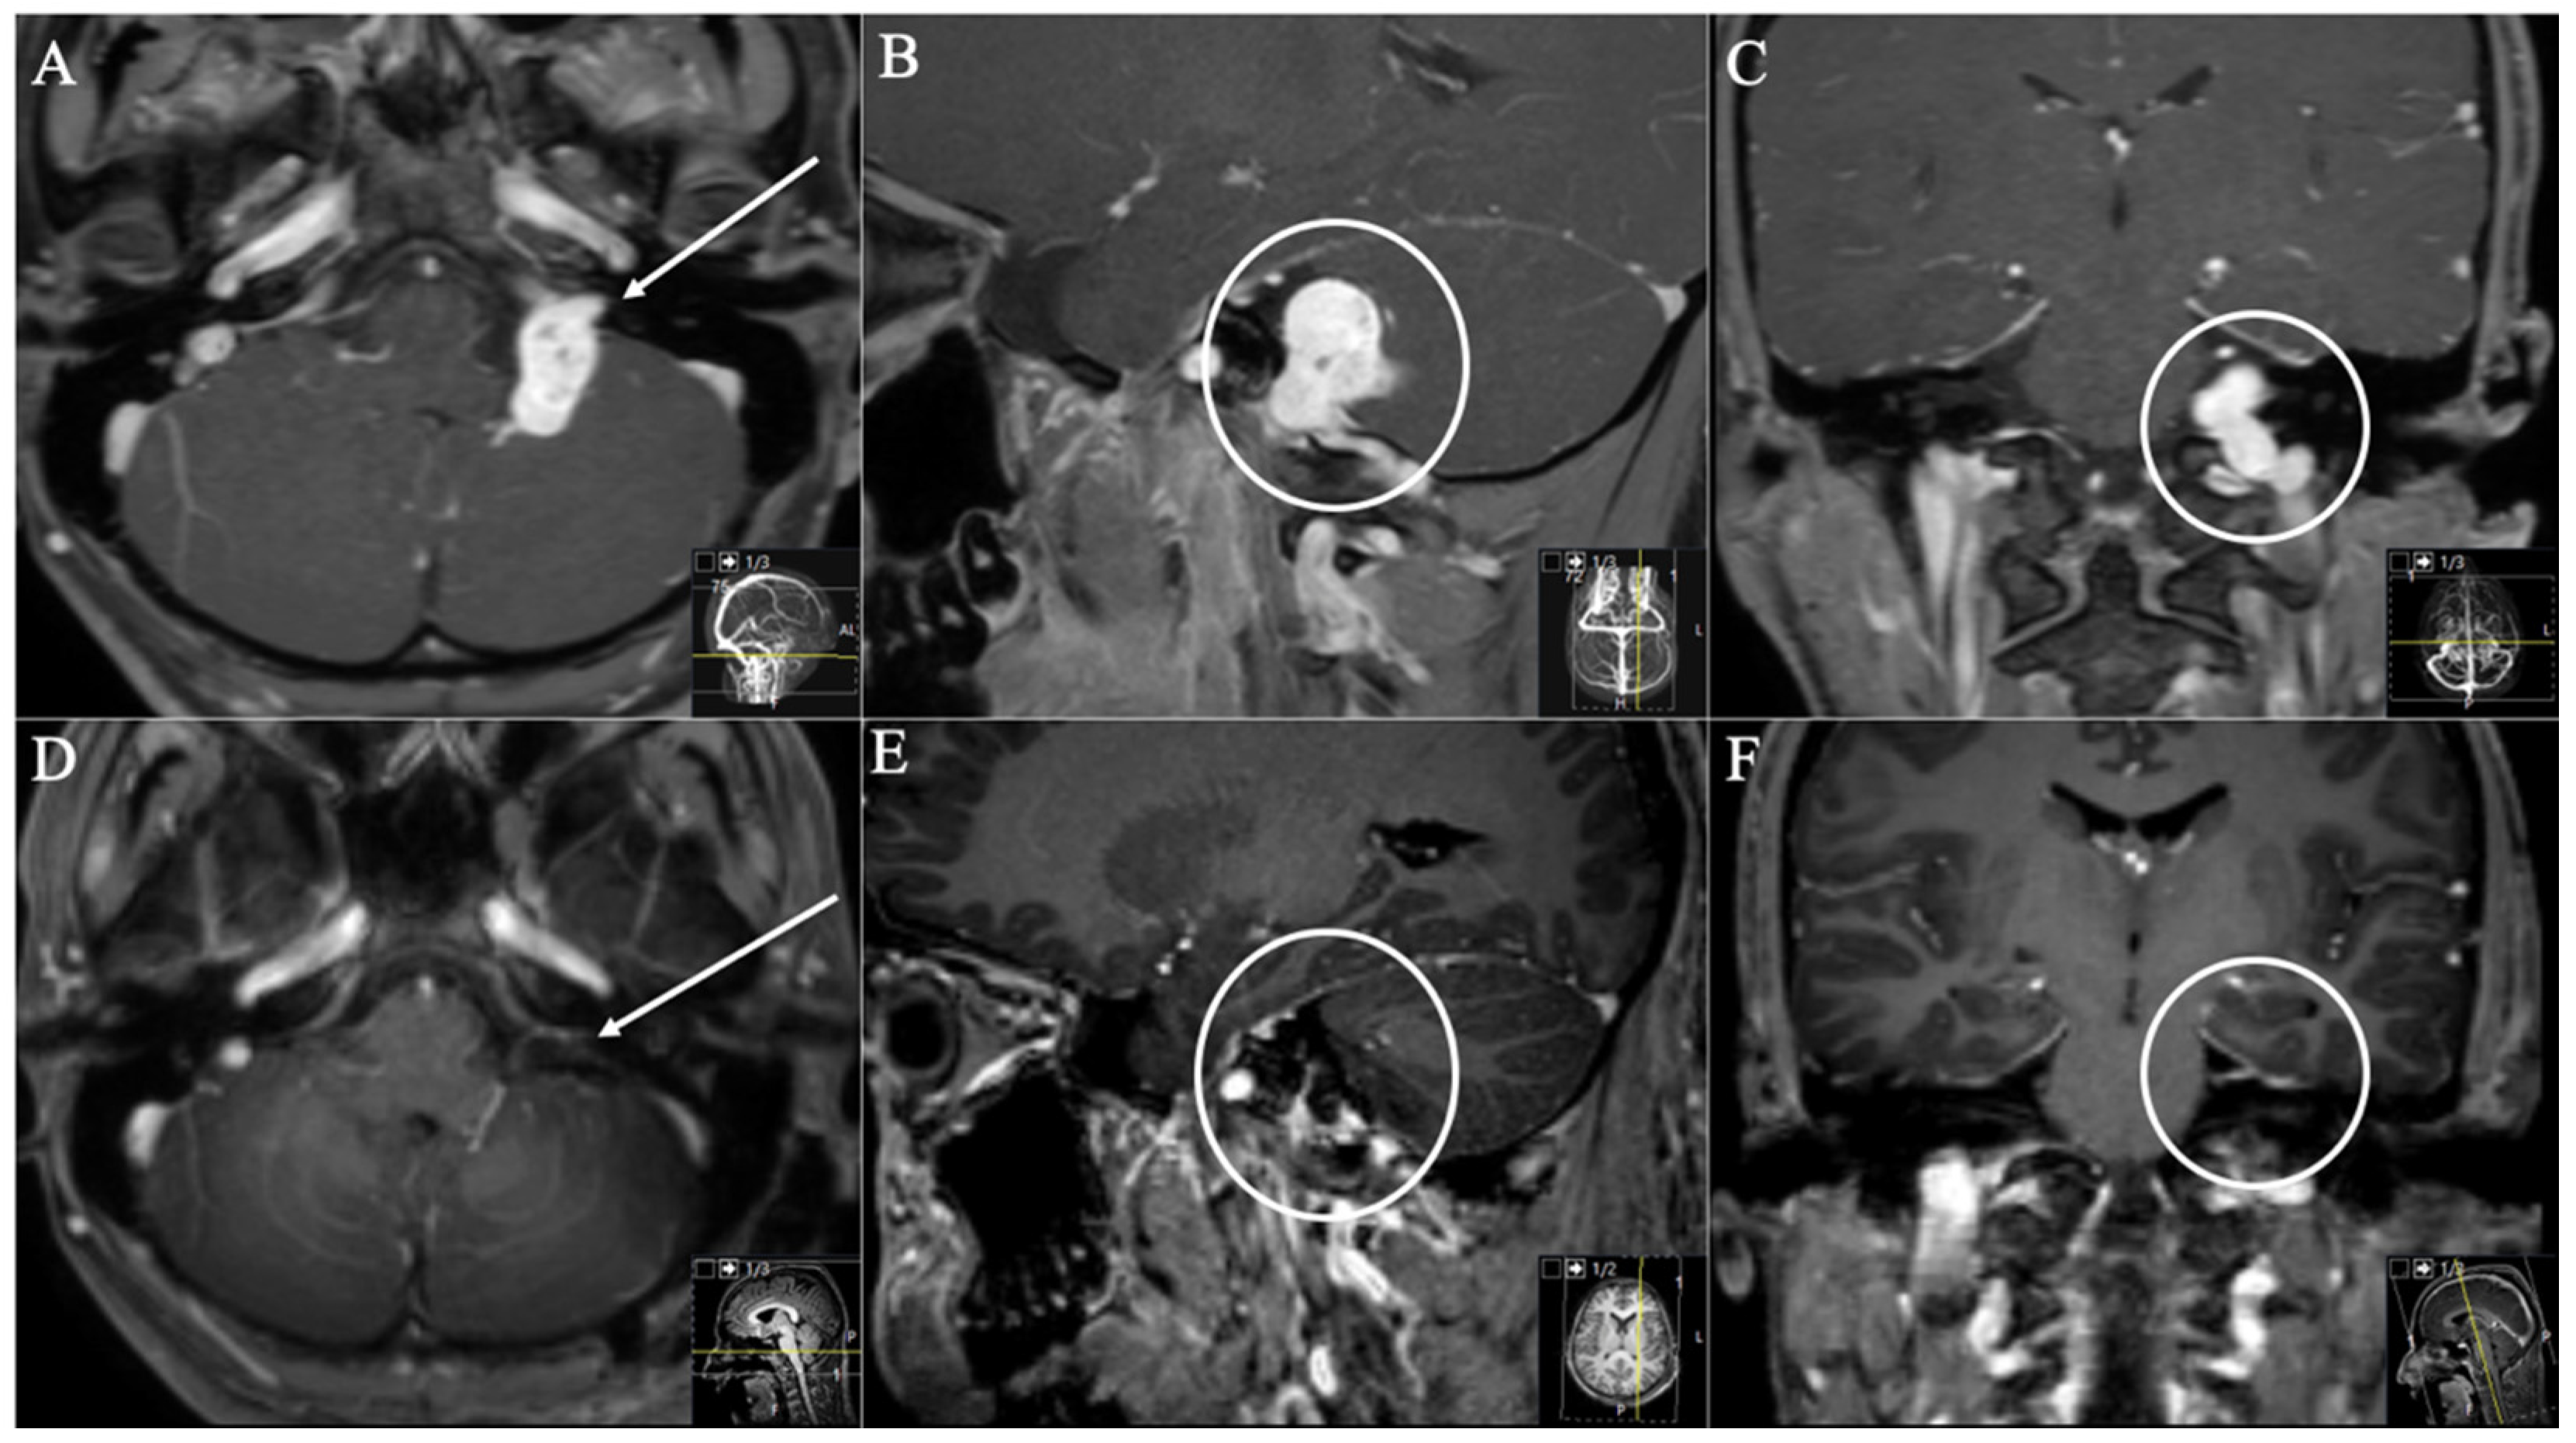

2.3. Surgical Approaches

2.3.1. Retrosigmoid Approach

2.3.2. Extreme Lateral Infrajugular Transcondylar (ELITE) Approach